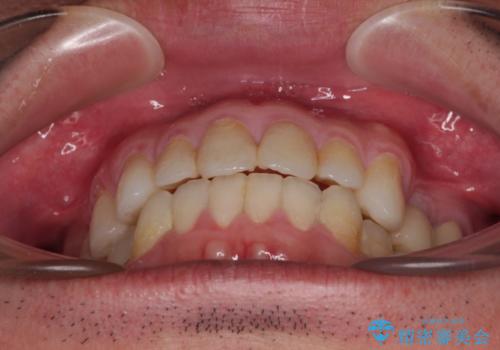

内側に転位した歯とボロボロのむし歯 インビザラインによる矯正治療とむし歯治療

- ボロボロのむし歯とデコボコの歯列を気にして来院された患者様です。

ボロボロとなっていた歯は抜歯が必要な状態でしたが、舌側転位している歯を移動させることで抜歯スペースを埋めることができるため、矯正治療により歯列を整えることとしました。

舌側転位の改善にインビザラインを用いるのはやや難易度が高くなりますが、前歯部のデコボコは軽度であったため、インビザラインによる矯正治療を行うこととしました。

矯正治療開始時に、インビザライン矯正の加速装置を購入されましたが、インビザライン自体をあまりしっかりと使用できず、4年間の治療期間となりました。